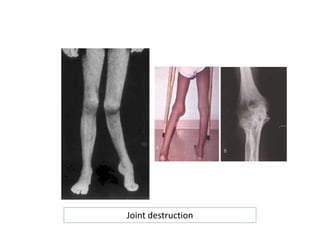

JOINT CONTRACTURES

Hemophilic arthropathy

“Target joint” = irreversibly damaged joint

with vicious cycle of injury and repeated

bleeding

Joint destruction